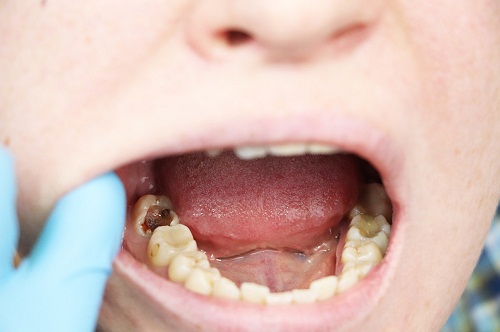

·繼發齲齒:補牙材料邊緣可能因清潔不當或時間推移出現微小縫隙,導致細菌滋生,形成新的蛀牙。這種情況在補牙後幾年內較為常見。

·填充物磨損或破損:補牙材料如樹脂或銀汞,在長期使用後可能磨損、脫落或破裂,暴露牙本質,引發敏感或疼痛。

·牙髓問題:如果原始蛀牙較深,補牙後牙髓(牙神經)可能因炎症或感染而出現問題,導致隱痛或劇烈疼痛,甚至發展為牙髓炎。

·牙齒裂痕:補牙後的牙齒可能因咀嚼硬物而出現微小裂痕,導致疼痛,尤其在受力時明顯。